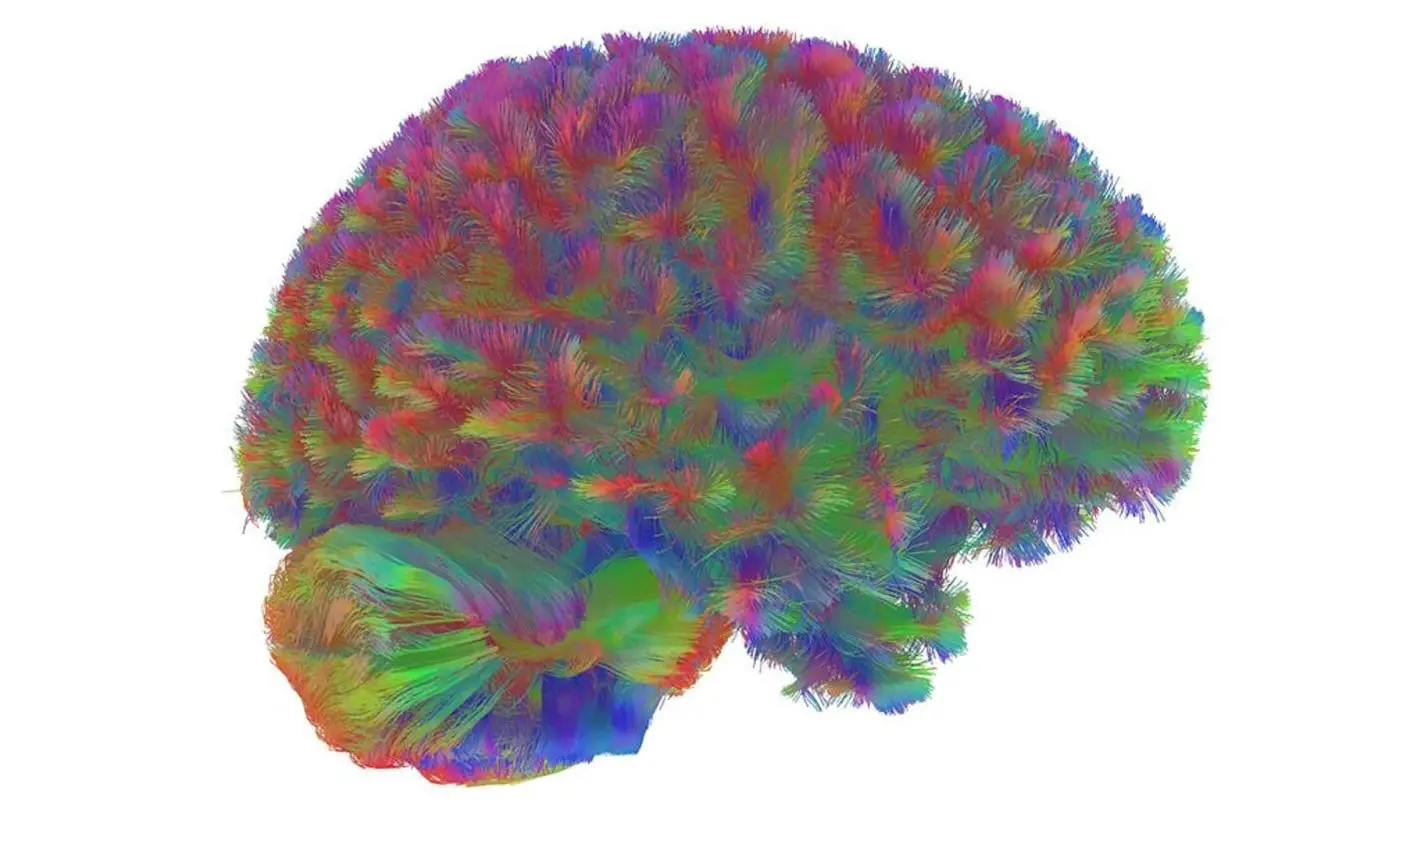

Исследование ученых Кембриджского университета проливает свет на удивительное развитие человеческого мозга на протяжении жизни, доказывая, что формирование его взрослой структуры завершается только после тридцати лет. Эта работа объединила данные более чем трех тысяч людей в возрасте от младенчества до 90 лет, позволяя определить ключевые этапы изменений мозга, а также разглядеть уникальные переломные периоды в его сложных структурах.

Анализируя данные, специалисты выделили пять последовательных фаз развития структуры человеческого мозга, между которыми проходят четыре значительных этапа перестройки. Именно в такие периоды внутри мозга происходит масштабная реорганизация связей и функций. Первый существенный переход случается около девяти лет — в это время ускоряется развитие мозговых сетей, и человек входит в подростковую фазу, сохраняющуюся до примерно 32 лет. Затем наступает продолжительный период взрослой стабильности, длящийся около трех десятилетий.

В начале жизни, в младенческом возрасте, мозг насыщен чрезмерным числом синапсов — специальных соединений между нейронами. В этом периоде идет активная оптимизация: одни связи постепенно исчезают, другие, более востребованные, получают дополнительное укрепление. Растут объемы серого и белого вещества, кора мозга утолщается, и формирование ее извилин практически завершается.

Когда человек проходит через подростковую стадию, наблюдается значительный рост белого вещества, что повышает точность и согласованность работы мозговых сетей. Происходит оптимизация внутренних и внешних связей между разными областями мозга, возрастает их согласованность: это фундамент для улучшения памяти, мышления, других когнитивных способностей. Переломный момент в районе 32 лет знаменует окончание подростковых изменений — и мозг входит во взрослое состояние с максимальной организованностью нейронных коммуникаций.

В течение зрелого возраста структура мозга остается устойчивой, без внезапных смен; однако изучения показали, что определенные области специализируются, становятся более автономными друг от друга. Это создает оптимальные условия для поддержки зрелых когнитивных функций и позволяет человеку эффективно адаптироваться к общественной, профессиональной деятельности.

Около 66 лет наступает новый этап, который специалисты определяют как раннее старение мозга. Здесь уже не наблюдается резких переломных изменений, но происходят постепенные корректировки в организации мозговых сетей. В самом пожилом возрасте — примерно к 83 годам — вступает финальная стадия, характеризующаяся снижением общего количества нервных связей, а роль некоторых специализированных областей возрастает.

Хотя детали последних этапов изучены не до конца, очевидно, что мозг продолжает меняться и адаптироваться даже в глубокой старости. Снижение числа связей происходит компенсаторно, чтобы поддерживать эффективность когнитивных процессов — и это подтверждает жизненную важность функций отдельных областей.